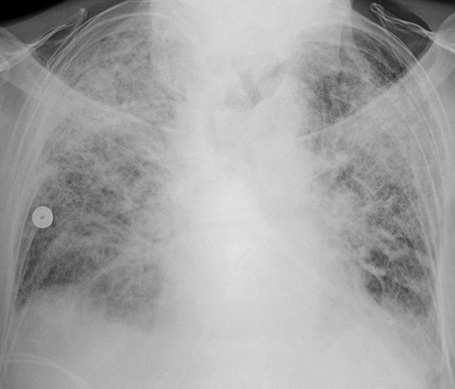

誘發(fā)急性呼吸窘迫綜合征的原因有哪些?在日常生活中有效的了解急性呼吸窘迫綜合征產(chǎn)生的原因,可以幫助我們更好的預防該疾病的產(chǎn)生,那么下面我們就來給大家介紹一下,一起來看看吧!

(一)肺水腫的產(chǎn)生 各種致病因素使肺血流灌注不足,直接損害肺泡、毛細血管上皮,引起肺泡毛細血管膜的通透性增加。血循環(huán)中的粒細胞、血小板及組織巨噬細胞釋放的各種炎癥介質(zhì)將加重上述損害。液體及蛋白質(zhì)等漏出血管外,導致肺水腫形成,影響通氣/灌注比率,導致低氧血癥。

(三)肺表面活性物質(zhì)減少 肺表面活性物質(zhì)襯附在肺泡表面.具有降低肺泡表面張力,瞅肺泡順應性,穩(wěn)定肺泡內(nèi)壓,防止肺毛細血管內(nèi)液體滲入肺泡內(nèi)的功能。它由廈型肺泡上皮細胞的線粒體合成及分泌的,其主要成分為二棕憫酮亞磷脂,大約18—24小時更新一次。 急性呼吸窘迫綜合征發(fā)病時,由于上述肺小血管痙攣及肺微小血管栓塞所致的肺血流減少,影響h型肺泡上皮細胞代謝,磷脂合成發(fā)生障礙;或由于水腫液、脂肪酸、氧個毒等因素直接破壞作用,使肺表面活性物質(zhì)減少,表面張力增高,肺泡縮小、陷閉,形成肺不張,同時肺毛細血管內(nèi)液體滲入肺間質(zhì)及肺泡。